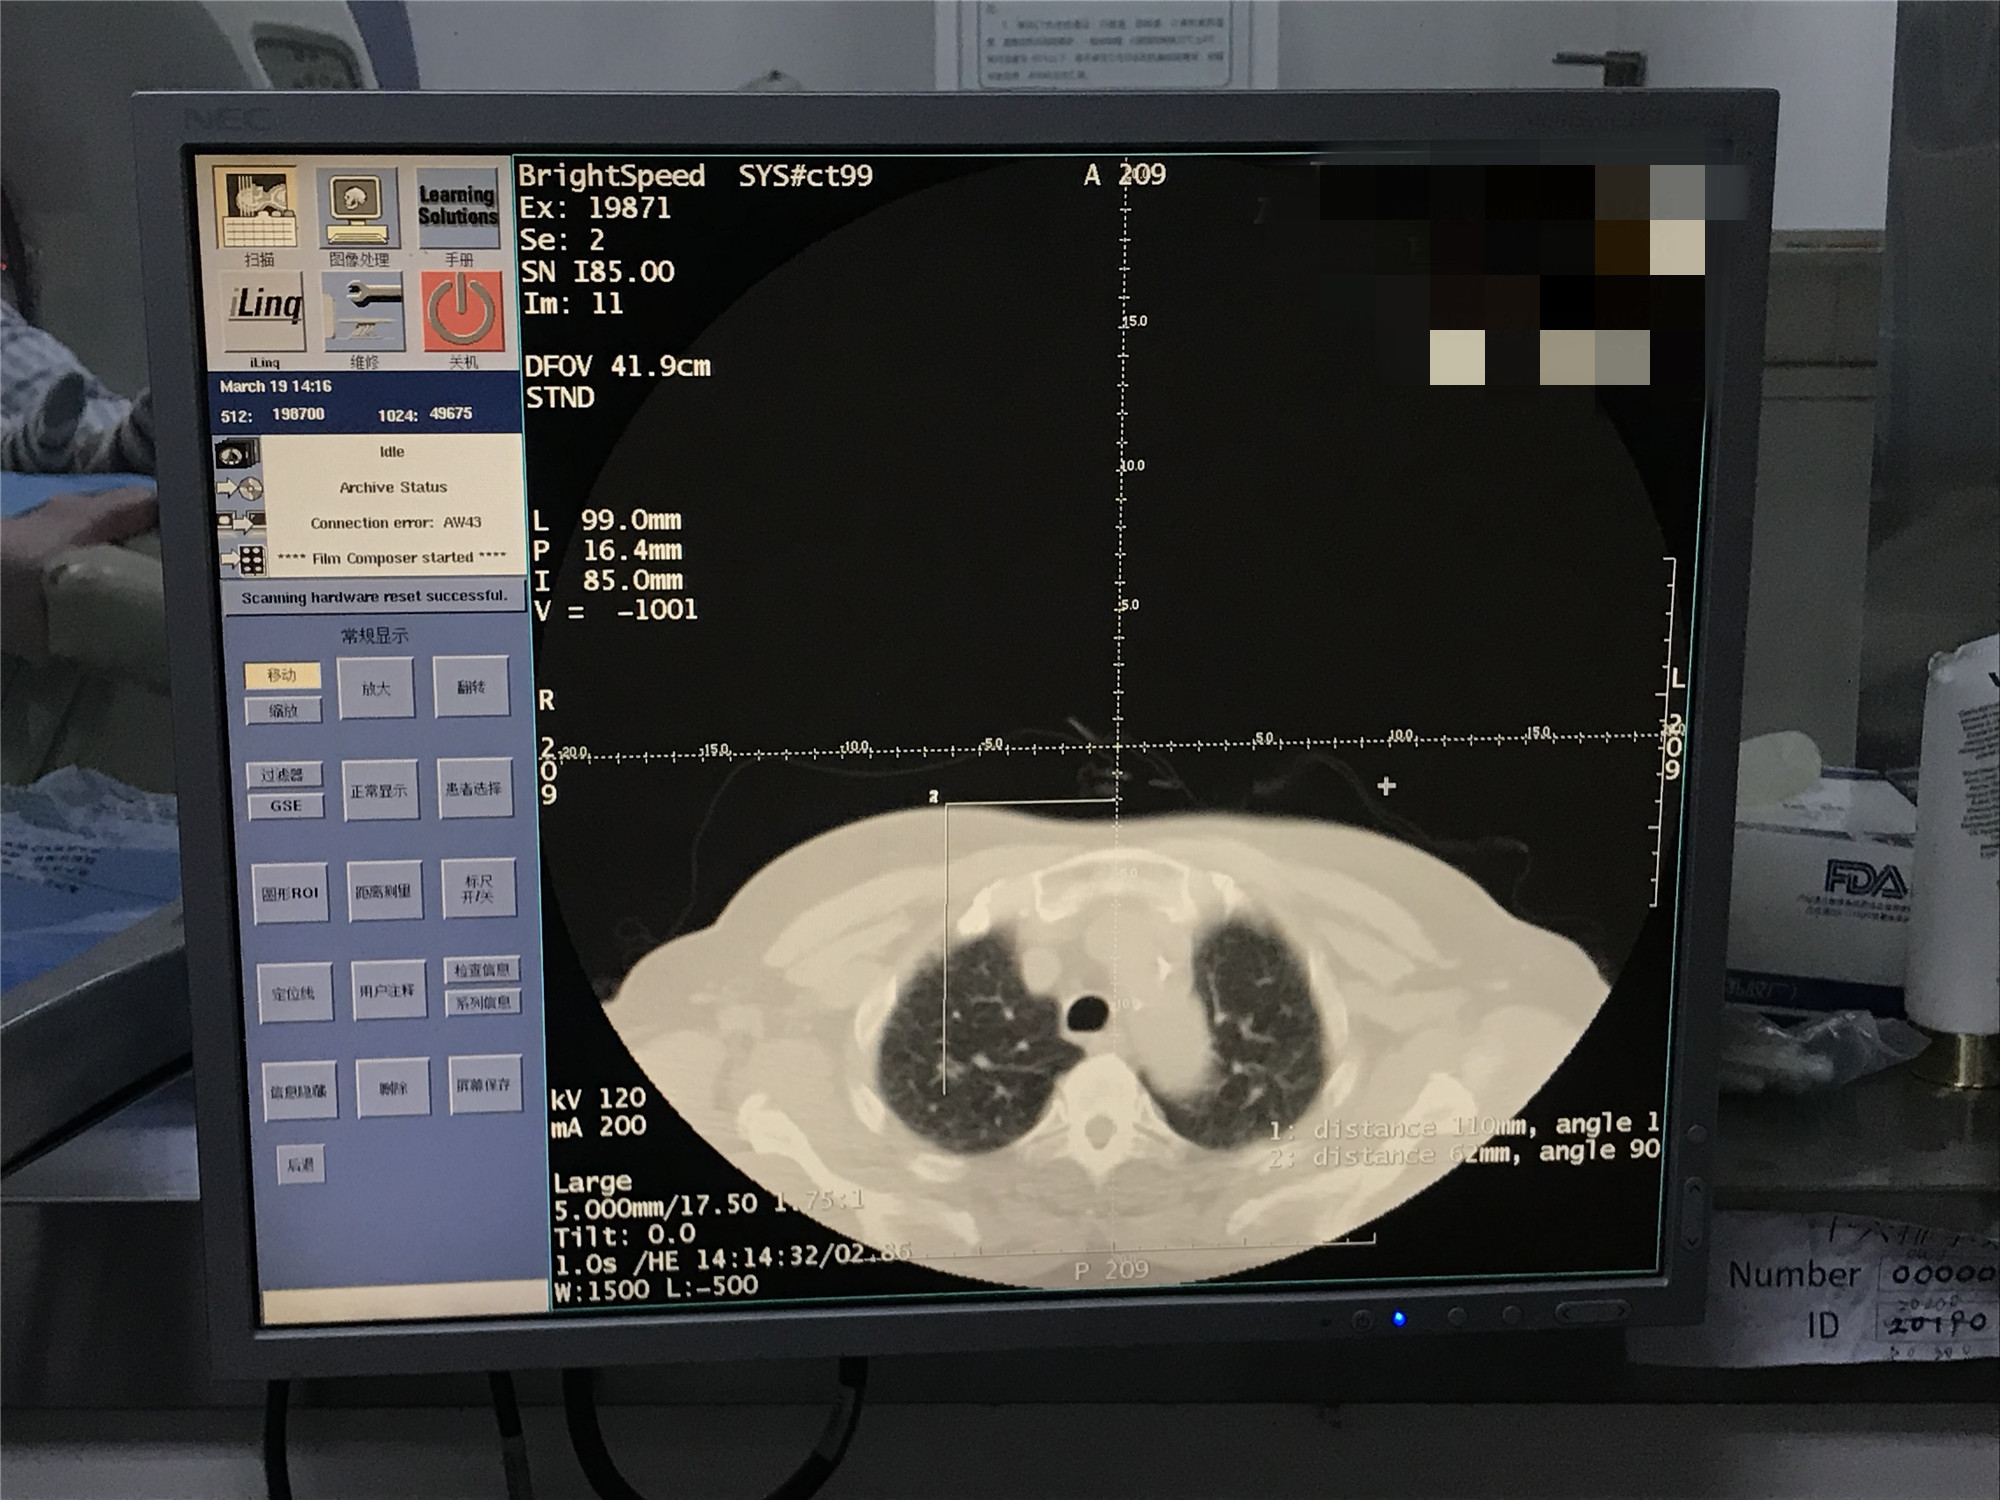

2021年3月份肺部氩氦刀手术

发布人:美国氩氦刀技术官方网站    发布时间:2021/9/22 15:44:51